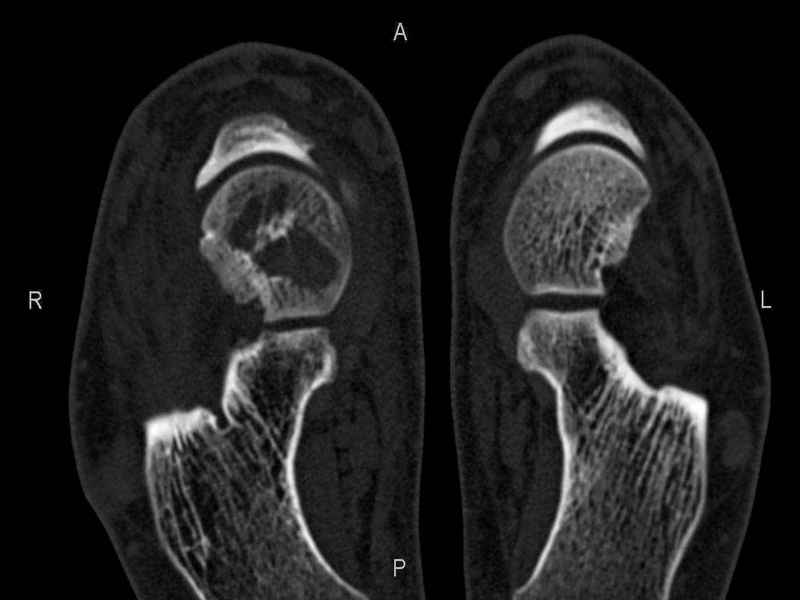

Уважаемые коллеги, обратился за помощью пациент, мужчина, 25 лет. С жалобами на болевой синдром в области голеностопного сустава и среднем отделе стопы. Травму отрицает. Со слов, болевой синдром в течении 1 года. Последние 1-1.5 мес периодически вынужден пользоваться костылями. После ограничения нагрузки боли уменьшаются.Соматически здоров. До появления болей активно занимался рукопашным боем. На СКТ картина рассекающего остеохондрита блока таранной кости, киста шейки таранной кости с признаками импрессии суставной поверхности. А также - разрастания переднего края б\берцовой кости сопровождающиеся клиникой импиджмент синдрома. Предполагаемый план лечения- удаление свободного фрагмента суставного хряща из трансмаллеолярного доступа с рассверливанием поверхности дефекта, кюретаж кисты шейки с заполнением полости биокомпозитом + дебридмент переднего отдела голеностопного сустава. Прошу высказать своё мнение, за и против, предполагаемого плана лечения. А также по возможности ответить на вопросы: 1. Есть ли необходимость в улучшении васкуляризации таранной кости (например подтаранный артродез). 2. Учитывая планируемое применение биокомпозитного цемента целесообразно ли заполнение им дефекта блока таранной кости с моделированием края суставной поверхности.

СТ чётко демонстрирует секвестр, но открыв сустав вероятно, что хрящ тарана окажется интактным и только пальпацией/ ЭОП можно будет

идентифицировать локализацию секвестра. Если вы с этим столкнетесь, то секвестрэктомию я бы предложил сделать не со стороны суставной поверхности тарана, а со стороны угла тарана, субхондрально кюрретаж стенок, разнонаправленную туннелизацию спицей или 1.1мм сверлом и заполнить дефект спонгиозным графтом.

- киста шейки тарана, как вы думаете, какова её природа : аваскулярный некроз? эхинококк?